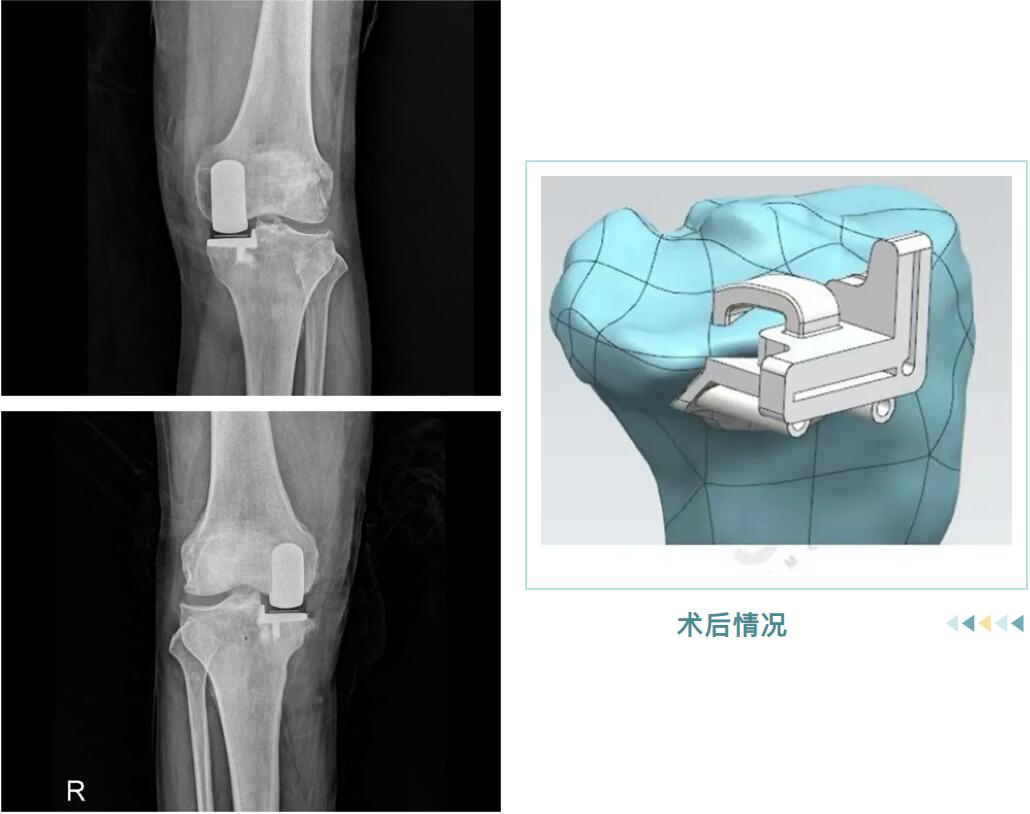

術(shù)后情況

它并非換掉整個(gè)膝蓋,而是用仿生“小墊片”精準(zhǔn)替換掉內(nèi)側(cè)磨損的軟骨面。手術(shù)僅處理病變部分,保留了您前后交叉韌帶和健康的軟骨,最大程度維持了膝關(guān)節(jié)原有的自然運(yùn)動(dòng)感和穩(wěn)定性。